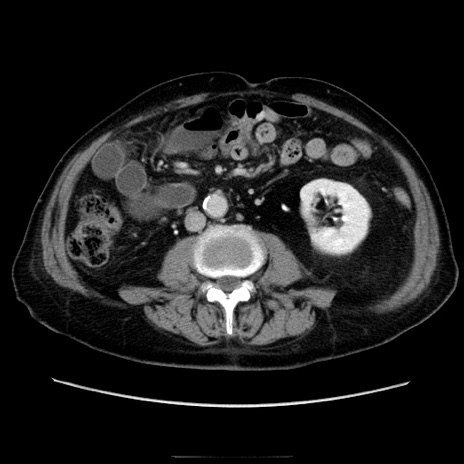

症例21(横断像)

【症例】70歳代男性

【主訴】腹痛

【現病歴】肝硬変・肝細胞癌にてかかりつけの方。約9時間前に食後より腹痛出現。症状が徐々に増悪し、嘔吐出現したため来院。

【既往歴】肝硬変、肝細胞癌(RFA、TACE後)

【身体所見】意識清明、表情苦悶様、BT 36℃、BP 129/78mmHg、P 88bpm、SpO2 97%(RA)、右上腹部から心窩部にかけて圧痛あり、反跳痛なし、筋性防御あり。

【データ】WBC 5800、CRP 0.16